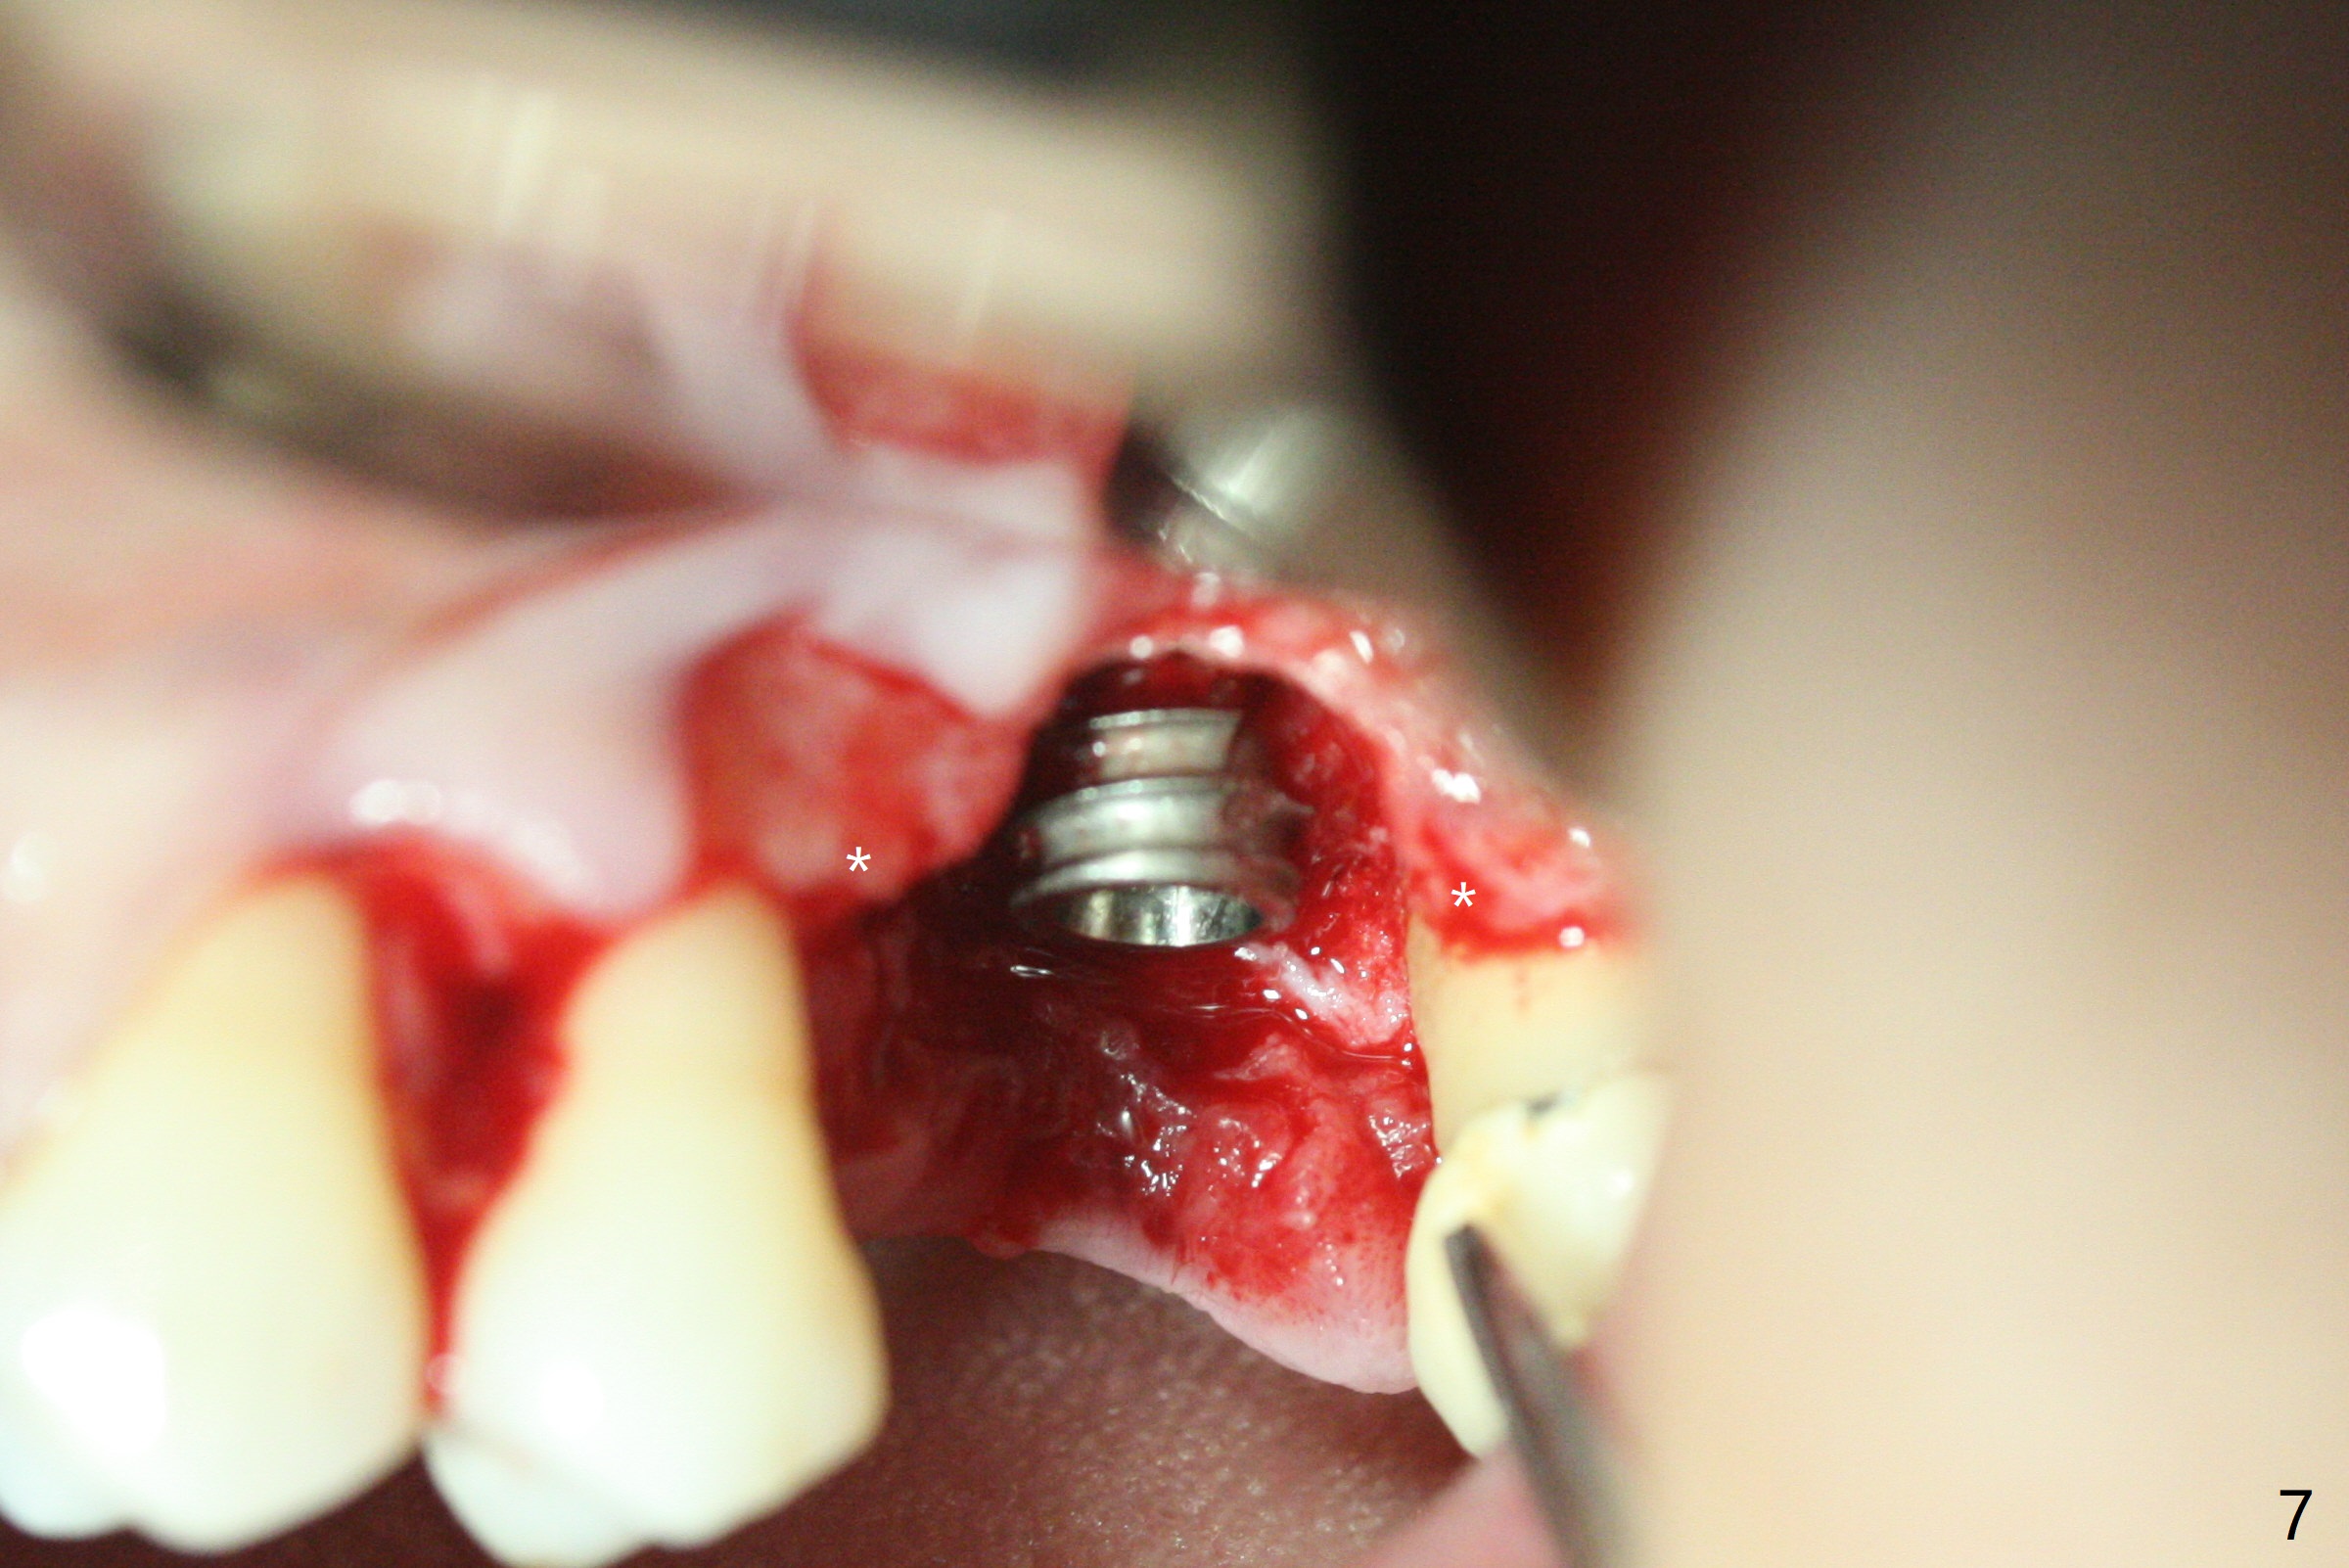

A 57-year-old woman complains of bad smell while use of water flosser between 11 and 21 months post cementation of implant crown at #14 (Fig.1,2). Bone loss is more obvious with CBCT (Fig.3,4), in spite of apparently normal gingiva around the implant after removal of the abutment and crown (Fig.5). In fact the buccal (B) gingiva is fragile with easy access to the underlying implant plateau. Following flap elevation, the bone loss is evident (Fig.6), but the implant plateau is slightly subcrestal (Fig.7 *). The exposed implant threads are covered with the 1st round of bone graft (Fig.8). After 2nd round of allograft (Fig.10-12) and collagen membrane, the flaps are approximated (Fig.9). The wound is covered by acrylic dressing. The latter is loose, but stays in place 1 week postop (Fig.13). Due to short neighboring teeth, the acrylic dressing is able to be removed with wiggling; it appears that the wound is healing (Fig.14). The dressing returns for another 2 weeks; some of the graft has been lost (Fig.15). The dressing does not return 7 weeks postop, since the wound is healing (Fig.16).